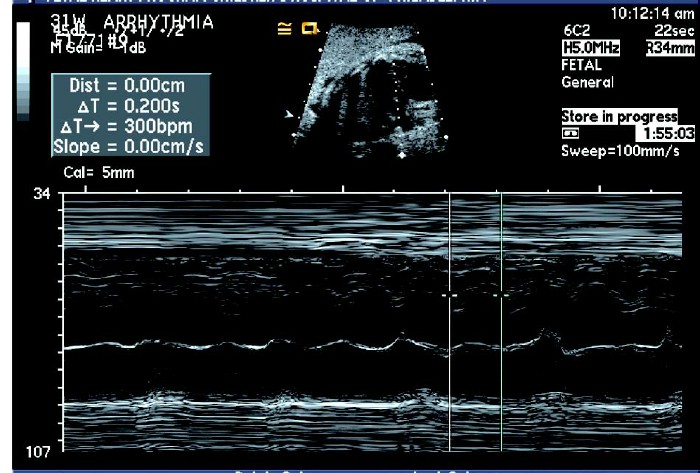

③心房颤动:房颤时心房率在300 ~ 500 次/ 分,心室率可正常也可达300 次/ 分。

④心房壁搏动曲线呈规律的锯齿样运动为心房扑动,心房壁搏动曲线细小无规律为心房颤动。